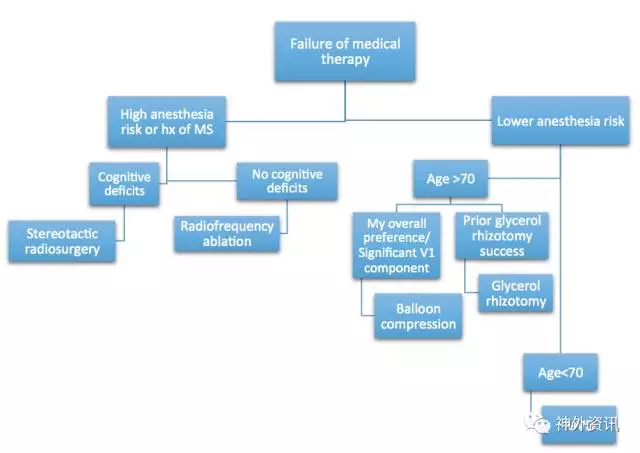

手术适应症

年龄大于70岁或有相关医学禁忌患者应该寻求创伤较小的经皮手术方法比如半月神经节球囊压迫术、射频消融术或者甘油毁损术。放射外科也是一种选择,但是在无药物干预情况下,缓解率较其他手术方式低。年轻患者(<40岁)术前应仔细评估,因为这组病人在上述任一种治疗方式后复发率相同。

姑息性破坏性手术通过对三叉神经根造成可控性毁损来达到缓解疼痛的目的。这类手术包括射频毁损术、甘油毁损术、半月神经节球囊压迫术以及立体定位放射外科毁损术。这些姑息性破坏性手术3-5年复发率约为50%。相反,微血管减压术对谨慎选择的病人,大概有80%的缓解率。效果可持续10-20年,复发率只有10%。

对于无法耐受微血管减压术的患者,笔者通常选择球囊压迫术,因为该手术易开展且起效快。若病人因为合并症而无法耐受全身麻醉,且不要求疼痛即刻缓解,笔者会推荐放射外科治疗。这项治疗不能即刻缓解疼痛,且在治疗期间患者仍需继续服用抗神经痛药物。

笔者用以下路径图来选择手术干预方式: